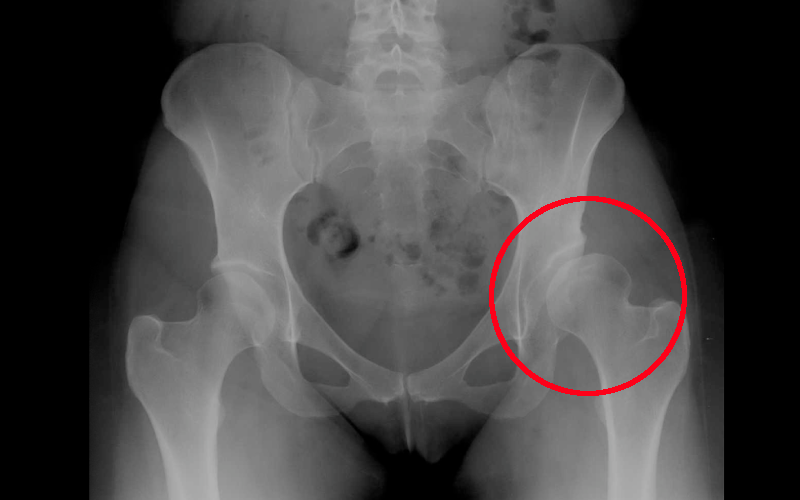

Oggi abbiamo operato un signore di 74 anni per la rimozione di uno spaziatore femorale, impiantato alcuni mesi fa, in sostituzione di una precedente protesi d'anca che si era "infettata" e che dava sintomi cronici di dolore, febbricola, fistolizzazione in sede della ferita chirurgica e fuoriuscita di liquido siero-purulento ad elevato contenuto di batteri. È una evenienza non frequente, ma fastidiosa.

La protesi d'anca viene impiantata quando sia presente una importante sintomatologia dolorosa all'articolazione coxo-femorale, in presenza di immagini radiologiche che mostrino la presenza di:

- displasia: condizione per la quale lo sviluppo dell'articolazione ha subito delle alterazioni per cui la testa del femore si trova in posizione diversa da quella normale e l'acetabolo ha una conformazione non in grado di accogliere la testa femorale.

Fai il paragone con l'anca controlaterale

- necrosi: condizione per la quale alcune aree della testa del femore si necrotizzano e si afflosciano determinando la perdita della struttura spongiosa e il supporto alla cartilagine articolare.

- artrite/artrosi: condizione per la quale uno stato infiammatorio acuto o cronico determina una alterazione delle cartilagini articolari ed una riduzione dello spazio articolare, con formazione di osteofiti.